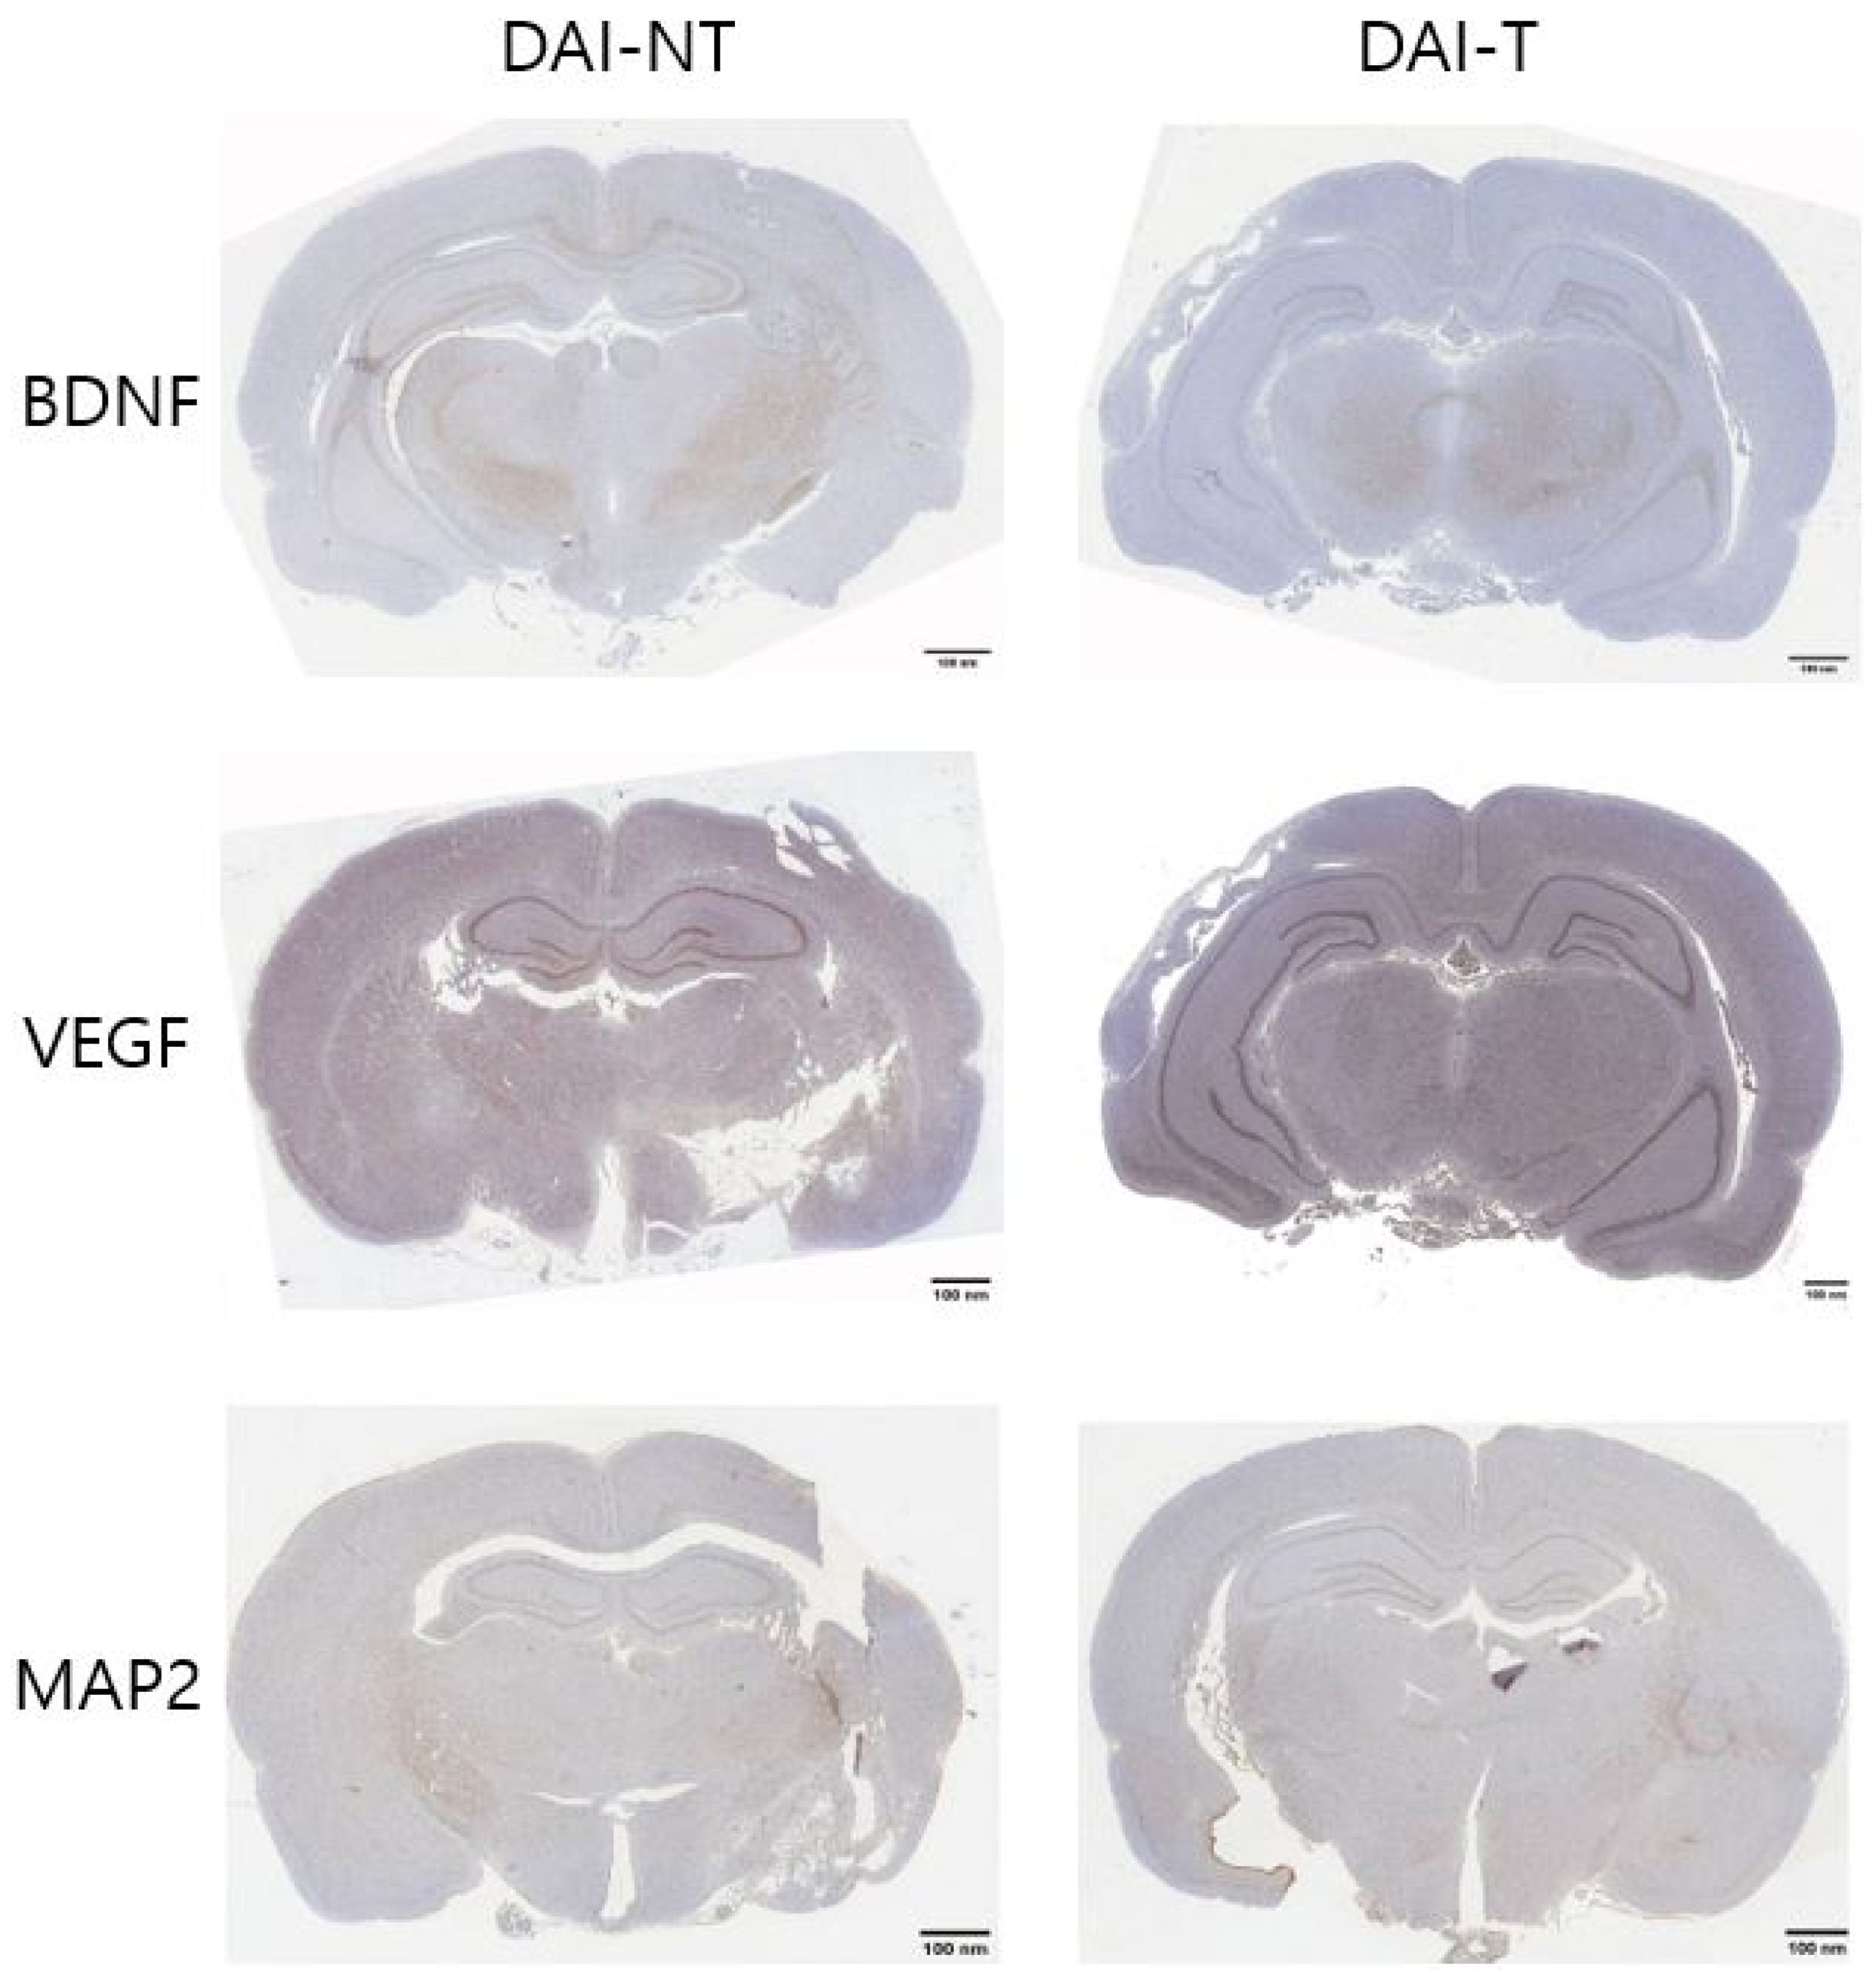

4.3. Immunohistochemistry

| Immunohistochemistry | Group | Area | Mean | % Area |

|---|---|---|---|---|

| BDNF | DAI-NT | 1,654,224 | 202.597 | 5.008 |

| DAI-T | 1,654,224 | 192.308 | 8.778 | |

| VEGF | DAI-NT | 1,654,224 | 168.547 | 8.711 |

| DAI-T | 1,654,224 | 158.346 | 12.105 | |

| MAP2 | DAI-NT | 1,654,224 | 204.679 | 10.475 |

| DAI-T | 1,654,224 | 202.148 | 12.814 |